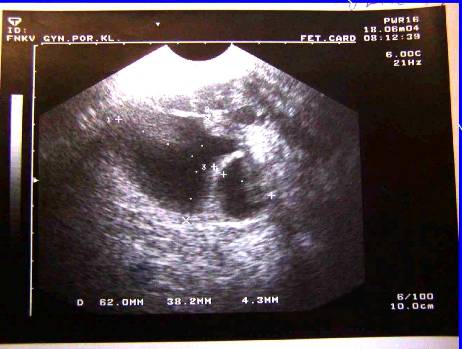

1. Recidiva (generalizace do dutiny břišní) –pac. M.T., tu markery, sono, laparotomia, peroperační biopsie

Recidiva (generalizace do dutiny břišní) –pac. M.T., tu markery, sono, laparotomia, peroperační biopsie

Recidiva(generalizace do dutiny do břišní) ––pac. M.T., sono, laparotomia, peroperační biopsie